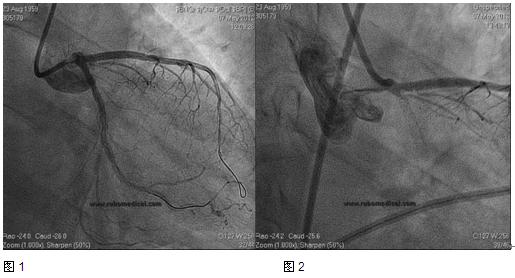

2012年5月7日行冠状动脉造影检查示:左前降支原支架内通畅,开口至近段偏心性狭窄80%,左回旋支弥漫性狭窄80%~90%,右冠状动脉弥漫不规则斑块,未见血栓,TIMI血流3级。于左前降支开口至近中段与前一支架重叠置入药物洗脱支架1个(Xience V 2.75×12mm);左回旋支远段置入药物洗脱支架一个(EXCEL 2.7×18mm),开口至中段置入药物洗脱支架1个(EXCEL 3.0×14mm),高压球囊对左回旋支近段支架内后扩张(图1)。术中患者生命体征平稳,返回病房。

术后15分钟患者再次诉胸部憋闷,不能平卧,伴大汗、恶心、呕吐、咳嗽粉红色泡沫痰,血压90/60 mmHg,心率102次/分,双肺水泡音,心电图示:I、avL、V1~V5导联压低0.2~0.4mV。在经主动脉内球囊反搏(IABP)的支持下行冠状动脉造影示:左回旋支开口急性支架内血栓形成,左前降支开口可疑血栓(图2)。血栓抽吸后于左主干至前降支置入支架一个(Xience V 4.0×12mm),左主干至前降支和左主干至回旋支行球囊对吻扩张。